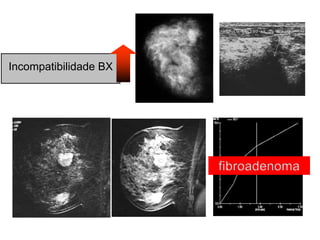

• Incompatibilidade BX

Incompatibilidade BX

Assimetria x Lobular